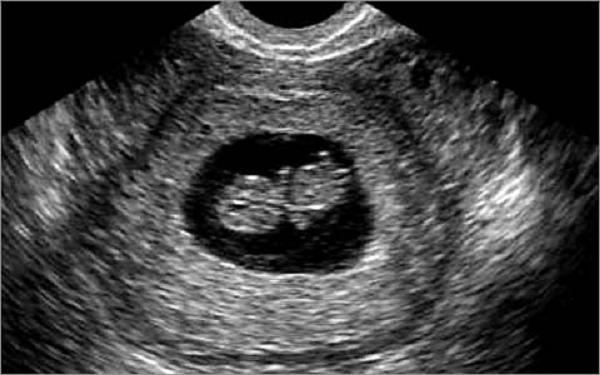

потому что как и в том посту так и в это напишу что врач что узистка дебилы у вас... понимаете если даже вы считаете что у вас срок 6 недель - это от зачатия!!! эмбриональный... значит акушерский как у большинства был бы он 8-9 недель... там на узи уже человек должен быть... вот узи 6 недель 3 дня от зачатия... какой тут эм брион искать.. идите в другую клинику.

6 недель от зачатия, это 8 акушерских недель...ктр плода 1-5-2 см, а пя около 4 см. Как узистка долго искала 2 см -го человека?... идите в нормальную клинику.